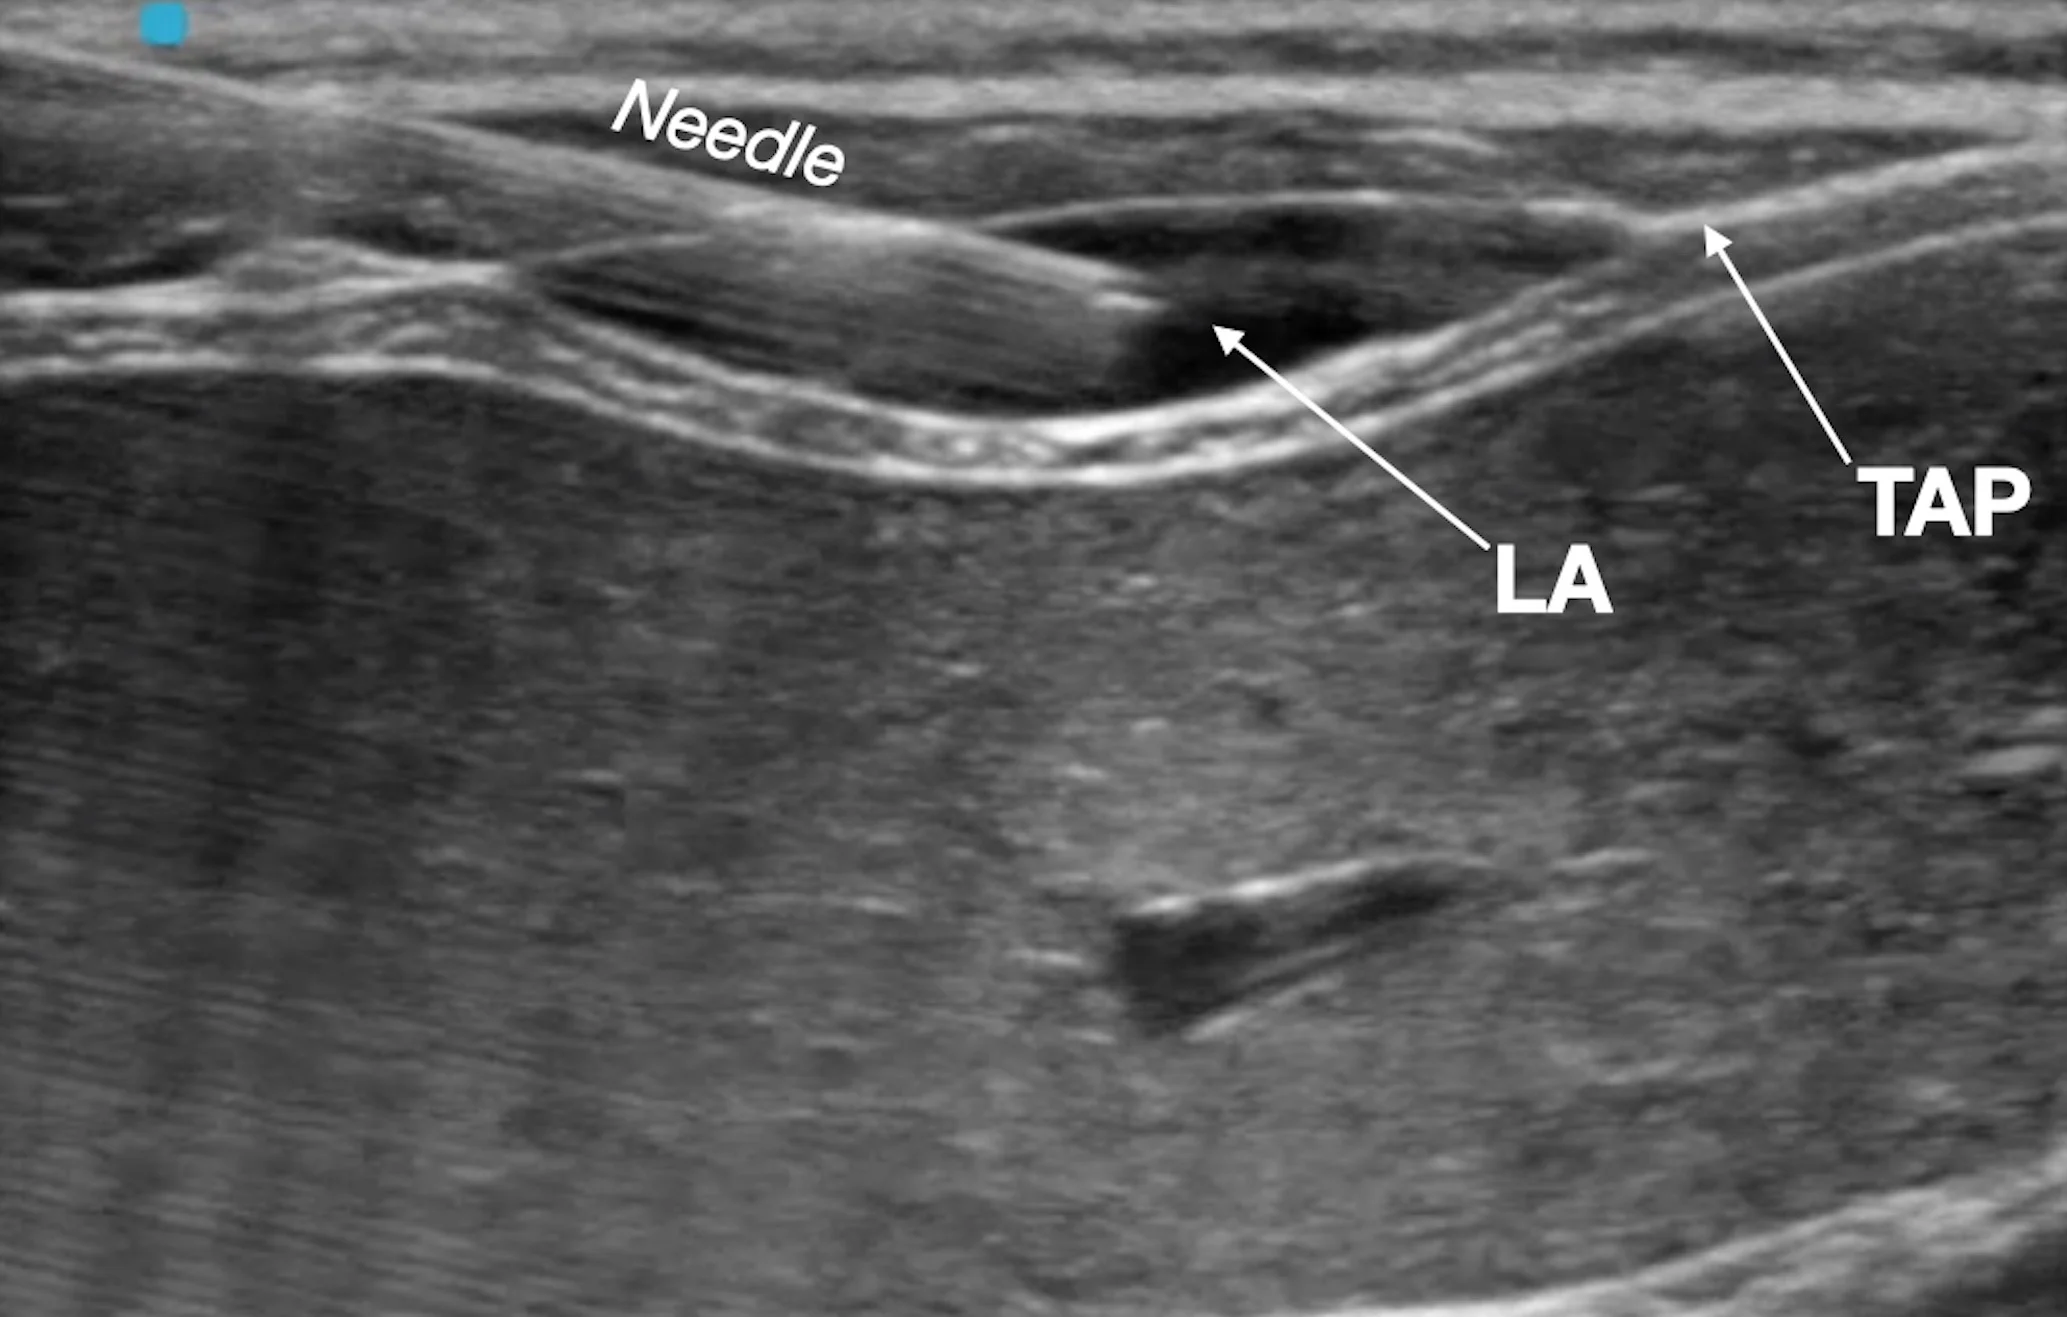

Step 11: Inject the Local Anesthetic for Cranial/Subcostal Block

Inject one aliquot (0.3 mL/kg) of the total calculated volume of the local anesthetic. Remove the spinal needle following injection.

Author Insight

The injected solution should separate the fascial plane, and anechoic fluid should be seen dissecting the fascia between the muscles. Gentle advancement of the needle into the target fascial plane during injection helps promote wider spread of the local anesthetic.